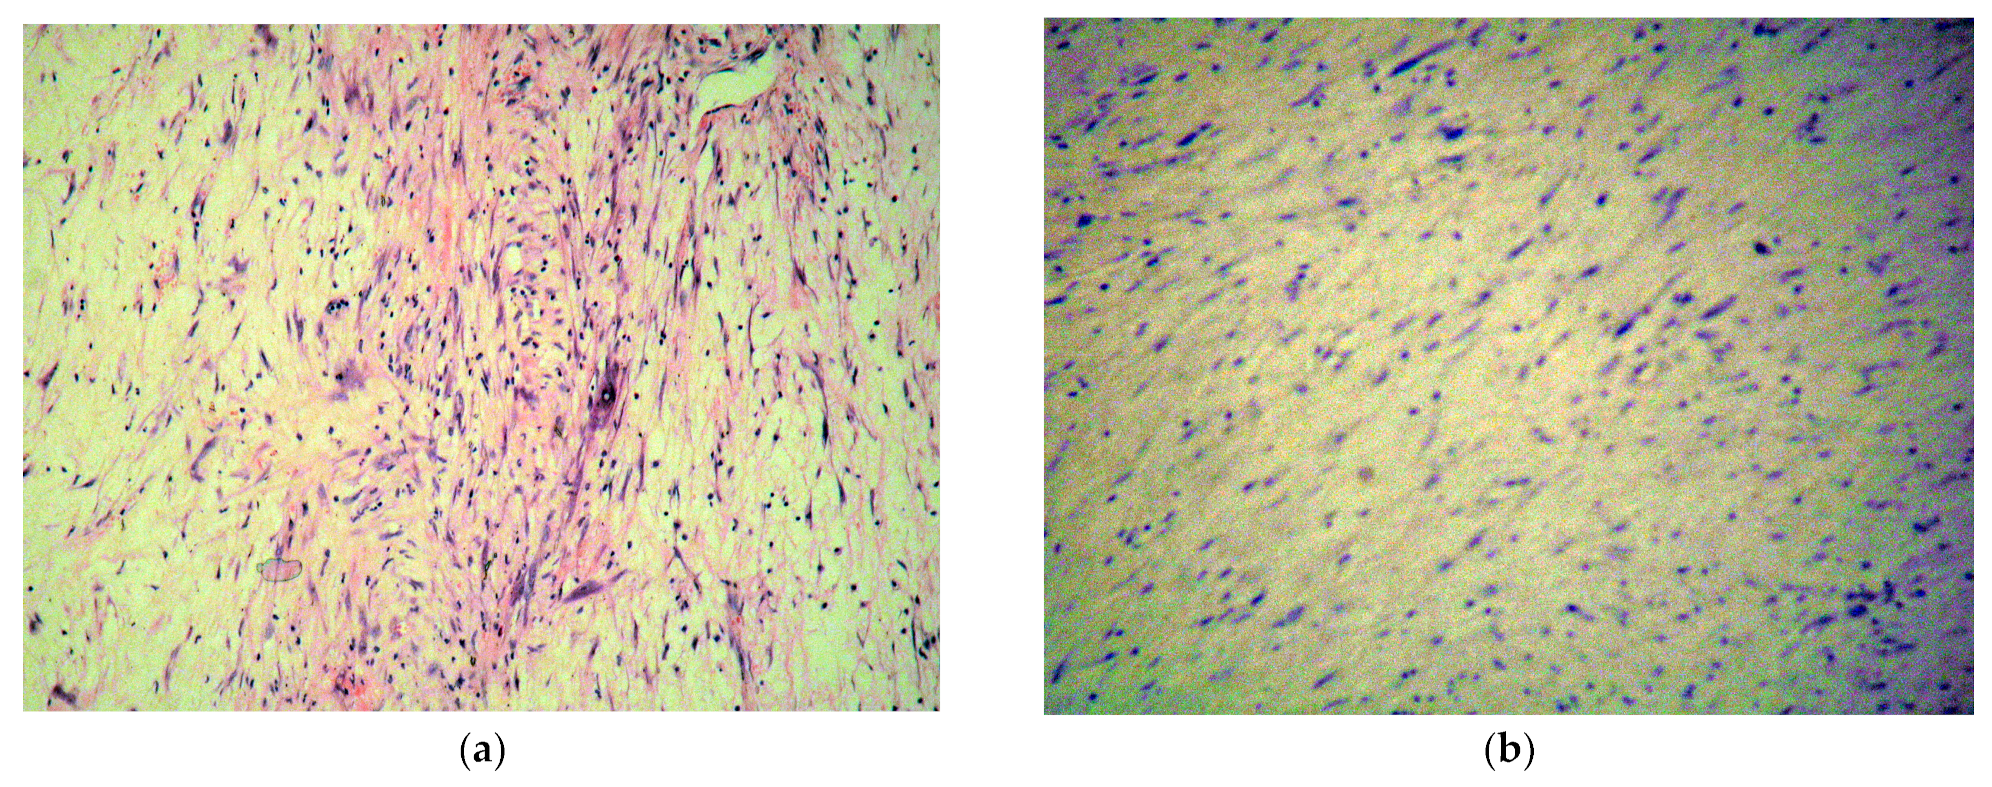

The pathology report described a mesenchymal proliferation composed of fasciculate and myxoid areas containing cells with elongated and stellate nuclei (Figure 7a), with extremely rare mitoses and a variable proliferation index of 10–20%, with positive resection margins. Focal necrosis was found in 10–15% of the tumor. Surprisingly, the immunochemistry showed positive actin, rarely positive desmin, inconclusive neuron specific enolase, negative CD31 and CD34, negative cytokeratin, negative calretinin (Figure 7b), and S100. The above-mentioned findings did not support the cardiac myxoma diagnosis but suggested a G1 low grade myxofibrosarcoma.

Figure 7. (a) Hematoxylin-Eosin staining showing mesenchymal proliferation composed of fasciculate and myxoid areas containing cells with elongated and stellate nuclei. (b) Immunohistochemistry staining with negative result for calretinin, thus infirming the initial myxoma diagnosis/lack of typical brown colored areas.